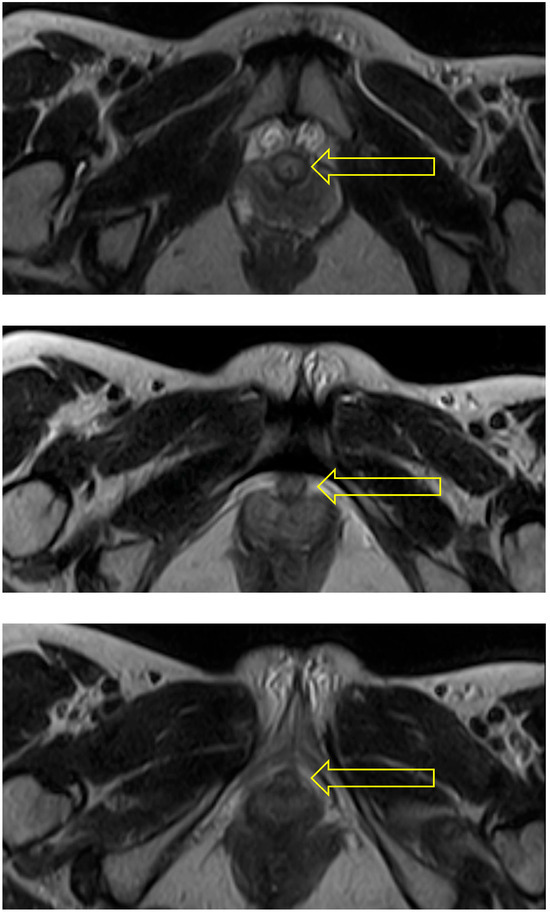

In the squat pose, Malasana, the urethra was seen as a circular structure at the bladder neck, but to be become oval in shape in the region of the mid-urethra (see Figure 4).

Figure 4. Squat: The two scans selected from this sequence show the urethra (indicated by arrow) as a circular (uncompressed) structure at the bladder neck (upper) and oval in shape and hence probably compressed at mid-urethra (lower).